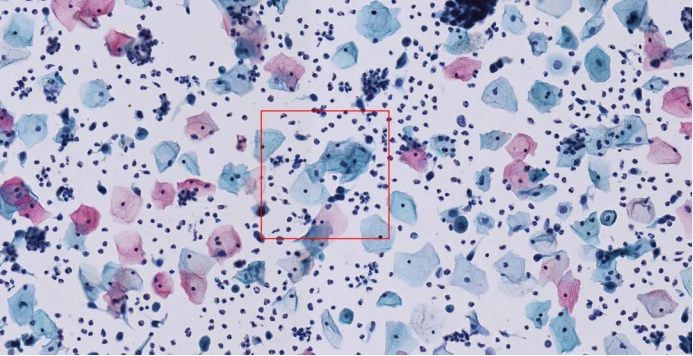

image.png

▲ 未明确诊断意义的非典型鳞状细胞(ASCUS)